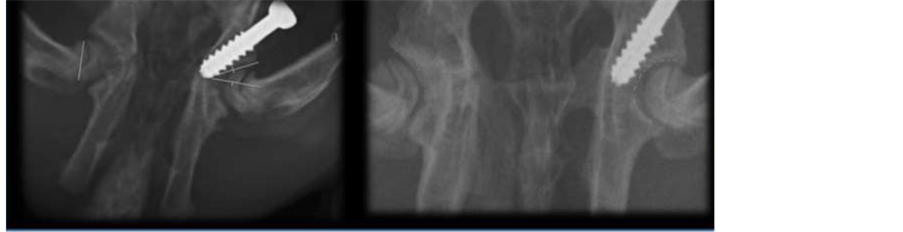

When comparing the median differences of the angles between groups evaluated at 12 weeks, a statistically significant difference was found in all radiographic measurements: an increase in Wiberg’s angle but a decrease in Acetabular index, acetabular angle of Sharp, acetabular depth index, and acetabular anteversion.

The differences of the results between groups are shown in Table 2 (Figure 8).

Figure 8. Radiographs of 12-week-old rabbits comparing right group-1 hips with left group-2 hips. (A) Lateral center-edge angle; (B) Acetabular index; (C) Angle of Sharp; (D) Acetabular depth index.

Here, we present preliminary data that support the hypothesis that selective growth arrest of the ilioischial arm of the triradiate cartilage (posterior epiphysiodesis) may alter growth and change the shape of the acetabulum (Table 2) showing how a selective percutaneous epiphysiodesis of the extra-articular part of the posterior limb of the triradiate cartilagesignificantly decreases the AI, the AS, and the ADI, while increasing the CE.